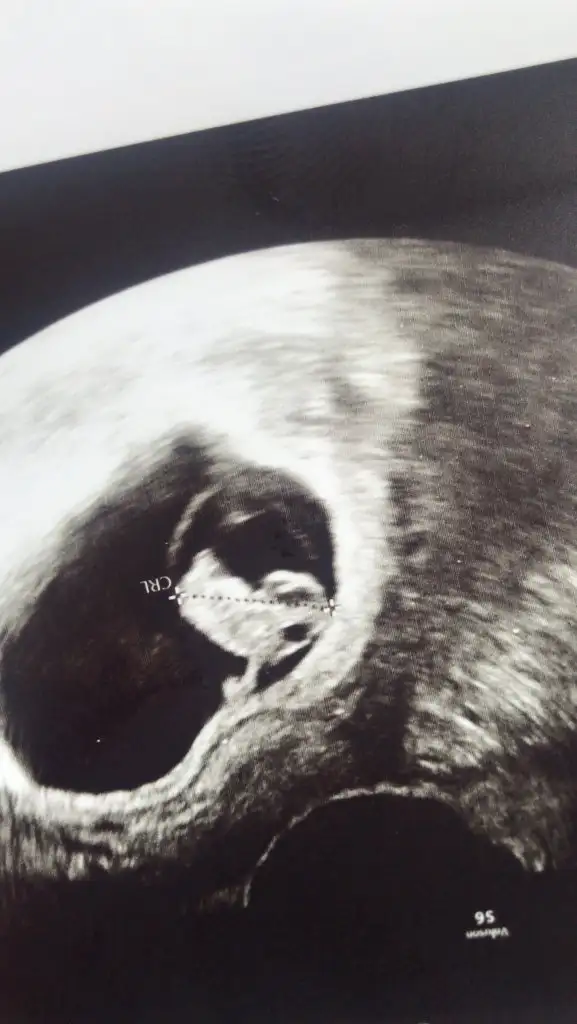

11 12 13 haftalar olmalıBenimkine de bakar mısınızEki Görüntüle 2828127

Benimkini de tahmin edebilirsinizErkek ve kız için 11 + 12+ yada 13 hafta usg görüntüsü olmalı açıklamalar asagıda yazıyorrabbim herkesin gönlüne göre nasip etsin inşallah .. ecmain

[/B]Eki Görüntüle 473828 gordugunuz gibi ust taraftaki simgedende anlasildigi gibi eger cikinti paralel ise kiz

yok 30°lik bir aciyla yukari dogru bakiyorsa %99 oglunuz olacak demektir simdi bi kac ornek resimler daha koyacagim kiziminkide dahil

Eki Görüntüle 473829 bu bir erkek bebek genital nub cikintisi gayet yukarda

Eki Görüntüle 473831 simdi burada cikintilara bakin eger bel popo cizgisine paralel ise kiz

yok 30 derecelik bir aciyla yukari bakiyorsa erkek